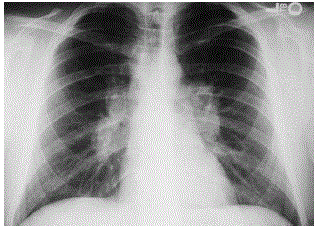

Uma paciente de 74 anos, parda, diabética e hipertensa de longa data, IMC 31 kg/m2, encontra-se internada para realizar cirurgia eletiva de ponte "by-pass" aorto-bifemoral devido à claudicação intermitente de membros inferiores. Sua pressão arterial elevou-se para 245/125 mmHg, desenvolvendo dispneia, estertores crepitantes bilaterais difusos que progrediram para bolhosos, esforço respiratório, Saturação de O2 87% e FC: 110 bpm. Sua temperatura axilar encontrava-se em 36,4ºC. RCR 3 tempos, B4. Ictus cordis no 4º espaço intercostal esquerdo na linha clavicular média. O ECG revelou ritmo sinusal, hipertrofia ventricular esquerda, sem alterações isquêmicas agudas. O Ecocardiograma com Doppler apresentou hipertrofia concêntrica do ventrículo esquerdo. A função sistólica global e segmentar do ventrículo esquerdo mantinha-se preservada. Havia déficit de relaxamento do VE e ausência de alterações no ventrículo direito. O quadro apresentado revaleva ausência de hipertensão arterial pulmonar. O RX de tórax demonstrou área cardíaca de tamanho normal e hipotransparência difusa do parênquima pulmonar. As enzimas cardíacas, glicose e função renal estavam normais. O hemograma apresentou discreta leucocitose. O diagnóstico compatível e a conduta a ser adotada no quadro descrito são, respectivamente,

Um homem de 55 anos, tabagista, apresenta tosse produtiva com períodos de exacerbação há alguns anos. Foi admitido na emergência com piora da tosse e hemoptise. Ao ser examinado constatou-se taquipneico, afebril, taquicárdico, normotenso, com baqueteamento digital. A ausculta pulmonar apresentava roncos difusos. A radiografia de tórax realizada gerou imagens lineares paralelas em bases (em trilho de trem) e imagens areolares em terço médio de ambos os pulmões, algumas com nível hidroaéreo. O diagnóstico provável é

Um homem de 30 anos procurou atendimento médico devido à alteração de radiografia de tórax encontrada quando fez exames de rotina (figura abaixo). A princípio não relatava queixas, mas na anamnese dirigida referiu tosse seca há cerca de 6 meses. HPP: paralisia facial periférica há 3 meses com boa recuperação. O diagnóstico provável é